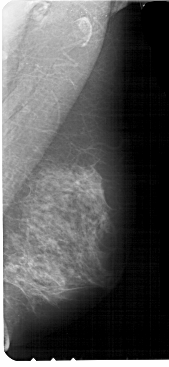

A_1885_1.RIGHT_CC

RIGHT_CC LINES 5296 PIXELS_PER_LINE 2401 BITS_PER_PIXEL 12 RESOLUTION 43.5 NON_OVERLAY